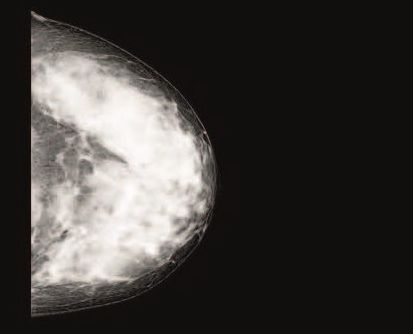

The European Society on Breast Imaging har anbefalet supplerende MRI skanning hvert andet til hvert fjerde år hos kvinder, der har tæt brystvæv, konstateret ved mammografi. Da brug af MRI scanning ikke vil være muligt at gennemføre i mange screeningsprogrammer, og da European Commission Initiative on Breast Cancer foreslår IKKE at implementere screening ved brug af MRI peger en artikel publiceret af en gruppe af skandinaviske forskere, herunder danske professor Elsebeth Lynge på alternative screeningsstrategier for kvinder med tæt brystvæv.

Artiklernes forfattere har analyseret forekomsten af såkaldte intervalkræfttilfælde (kræft opdaget mellem 2 mammografiscreeninger) samt tid fra screening til diagnosen brystkræft i tæt brystvæv. De har undersøgt mammografidata fra 508.536 mammografier udført i Norge på 213.105 kvinder mellem 2007 og 2019. Kvinder, der blev screenet i 2019, blev fulgt i to år med henblik på at opdage såkaldte intervalkræfttilfælde.

Den endelige population, der blev undersøgt, udgjorde 504.466 negative mammografier, 3.125 brystkræfttilfælde opdaget ved mammografi og 945 intervalkræfttilfælde.

Konklusionen på undersøgelsen er, at hvis det ikke er muligt at gennemføre supplerende MR skanninger hos kvinder med ekstremt tæt brystvæv, så kan en årlig screening af kvinder med ekstremt tæt brystvæv reducere forekomsten af brystkræfttilfælde mellem screeninger og samtidig øge sensitiviteten af screeningsprogrammet. Undersøgelsen er publiceret i artiklen: "Mammographic density and interval cancers in mammographic screening: Moving towards more personalized screening," i The Breast/ Volume 69, June 2023